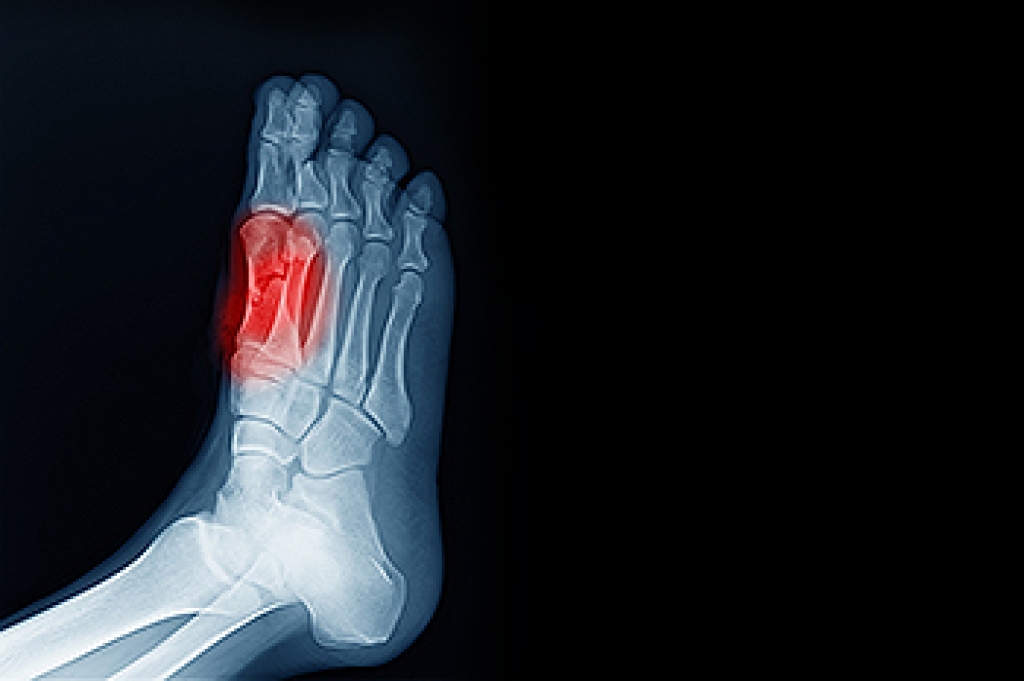

Foot and ankle injuries are a common occurrence when it comes to athletes of any sport. While many athletes dismiss the initial aches and pains, the truth is that ignoring potential foot and ankle injuries can lead to serious problems. As athletes continue to place pressure and strain the area further, a mild injury can turn into something as serious as a rupture and may lead to a permanent disability. There are many factors that contribute to sports related foot and ankle injuries, which include failure to warm up properly, not providing support or wearing bad footwear. Common injuries and conditions athletes face, including:

Sports related injuries are commonly treated using the RICE method. This includes rest, applying ice to the injured area, compression and elevating the ankle. More serious sprains and injuries may require surgery, which could include arthroscopic and reconstructive surgery. Rehabilitation and therapy may also be required in order to get any recovering athlete to become fully functional again. Any unusual aches and pains an athlete sustains must be evaluated by a licensed, reputable medical professional.